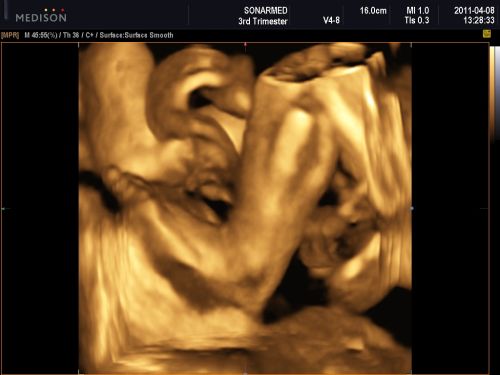

Amúgy nemrég voltam uh-on, és csücsült a baba, kezdek ideges lenni, mert a 18. héten voltam utoljára, akkor mondták lánynak, most meg ugye nem látszott, és mindent lányosat szereztünk be, a szoba is az, szóval most először várom a köv. uh-ot, ami a 36.-on lesz.

A nagylányom pedig összeszervált egy streptococcust, torokgyuszi formájában, itthon van még egy hetet, és nyűglődik, mert még pár napig nem engedem ugrálni, meg játszóterezni. A babának meg lassan örülnöm kell, ha nem lesz két feje és hat lábujja, tekintve, hogy az összes létező veszélyes fertőzést hazahordták a gyerekeim (emlékeztek, volt bárányhimlő is...).Azt mondták uh-on, hogy minden oké, de azért én már várom, hogy megnézzem, átszámoljam....